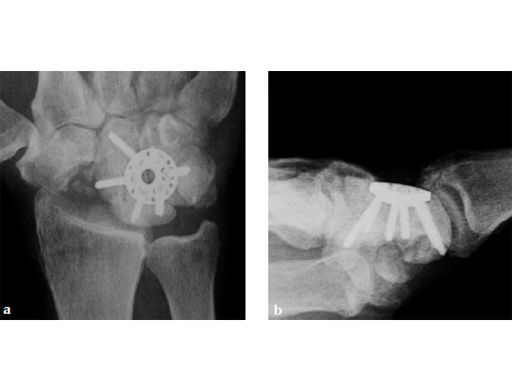

Case 2: Early degenerative wrist stage 3 secondary to a necrotic and collapsed proximal pole nonunion.

Case provided by Ariane Scheller, Berlin, Germany

Fig 1ab Preoperative x-rays. Note the carpal collapse a a b nd DISI deformity.